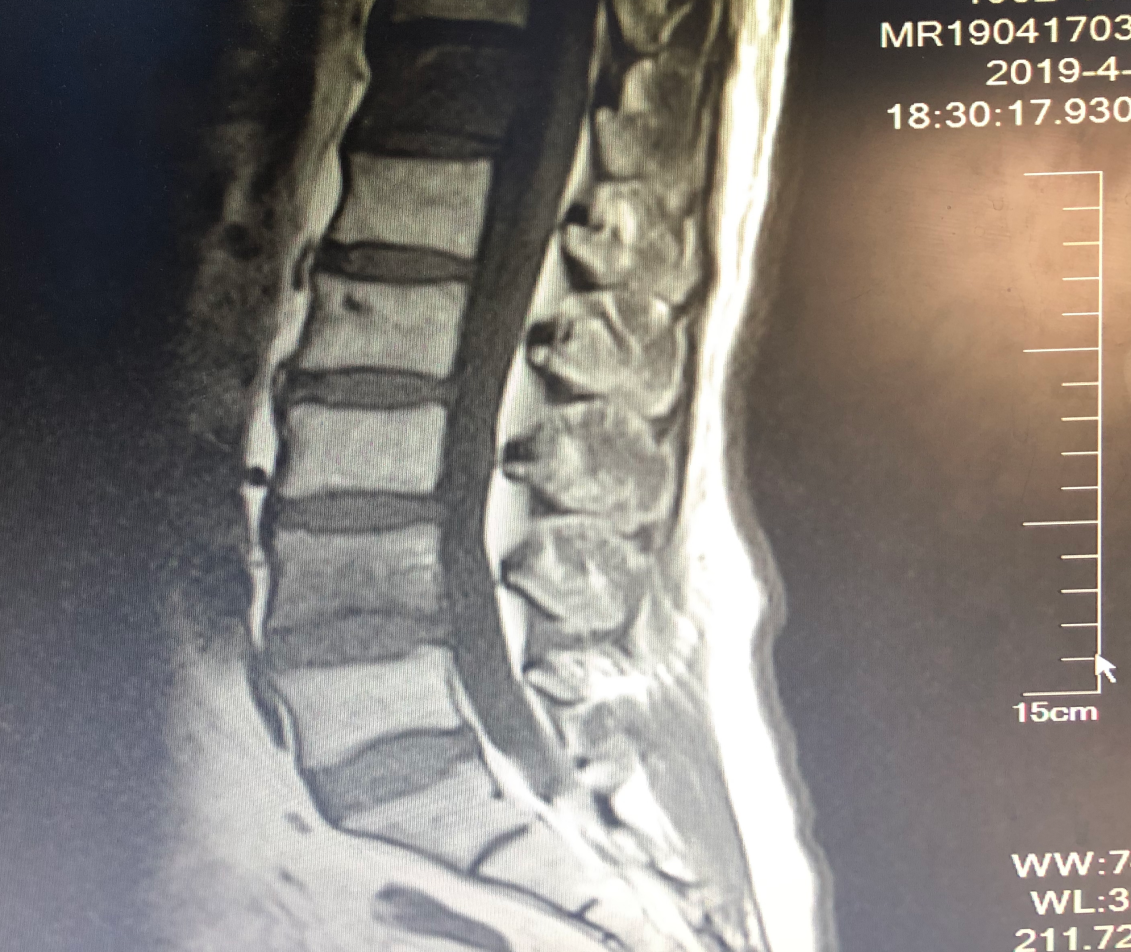

图4. 一线化疗2个周期后复查新发骨转移

图9. 信迪利单抗治疗3周期后腰椎骨转移缓解